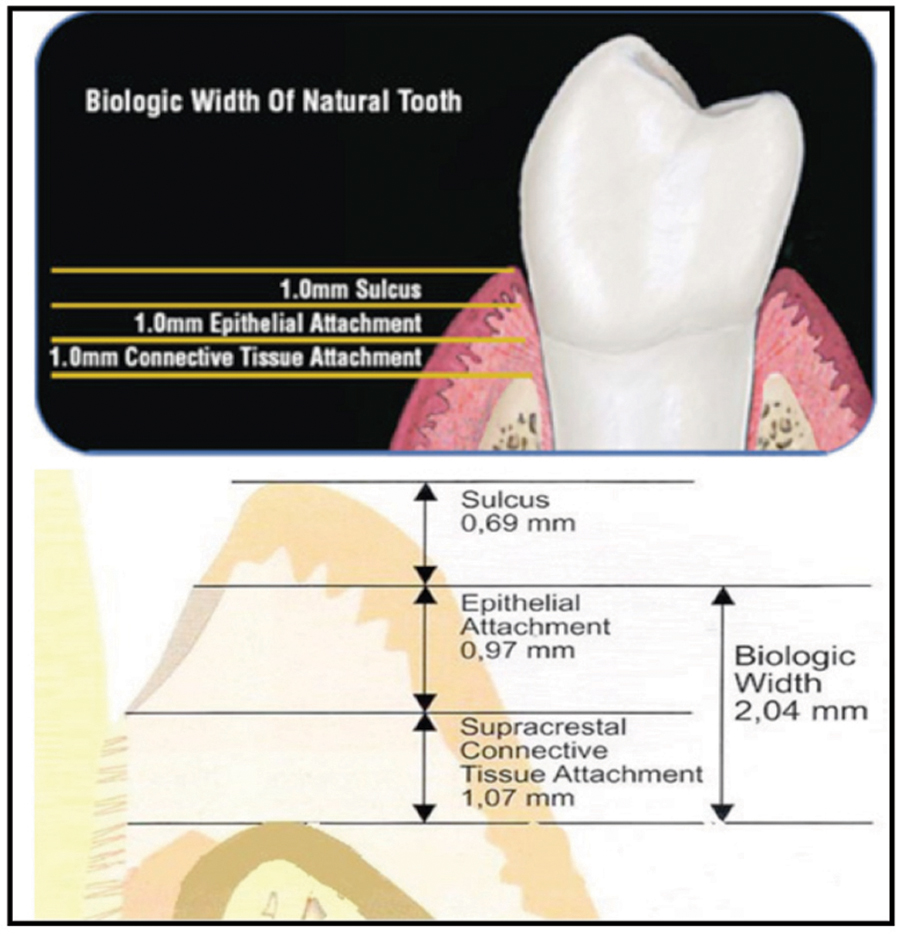

Among the most important requirements in esthetic dentistry is the presence and shape of the interdental papillae. In a recent article in the European Journal of Prosthodontics and Restorative Dentistry1, absence of interdental papillae (“black triangles”) was rated, as the third most disliked esthetic problem behind only visible anterior caries and visible anterior black crown margins. To understand how papillae get their shape and volume, we need to review the concept of the Biologic Width (BW) first described by Gargiulo, Wentz and Orban2 and later refined by Vacek3 and Choquet4 (Fig.1).5

The BW is the term used to describe the sum of the connective tissue attachment height (approximately 1.0 mm) and the epithelial attachment height (approximately 1.0 mm) around a natural tooth (averages 2.04 mm). The third component not part of the BW but related to tissue height is the gingival sulcus. A healthy sulcus measures approximately 1.0 mm midfacial and 2.0 – 3.0 mm interproximally. The sum of the BW and sulcus determines the tissue height above the osseous crest (bone). This averages 3.0 mm mid-facially and 4.5 – 5.0 mm interproximally but may vary from individual to individual and from tooth to tooth.

The extra 1.5 – 2.0 mm of tissue height interproximally is due to the interproximal contact factor and is a direct result of compression of interproximal tissue between adjacent teeth which effectively ‘squeezes’ 1.5 to 2.0 mm of tissue height beyond the midfacial height, giving rise to the 5.0 mm papillae criterion as referenced by Salama/Garber6, Tarnow7 and Choquet4. It is this interdental tissue height of 4.5 to 5.0 mm above the osseous crest that we refer to as the interdental papillae. Recently Hae-Sung Cho8 et al reviewed the effects of root on the existence of interdental papilla and found that root proximity has a direct effect on the presence of papilla.